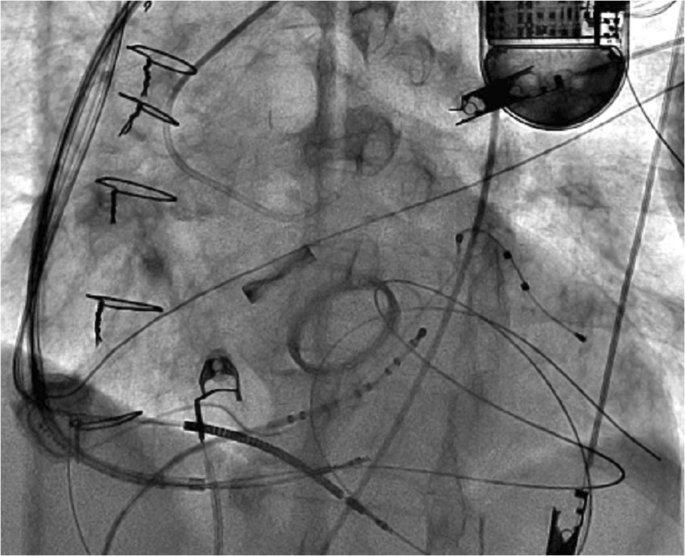

手术在全身麻醉下进行,通过左侧锁骨下静脉穿刺将LBBAP导管送入右心室。手术过程中使用LBBAP导管和三维弯曲传导导管进行引导。Tendril 2088TC 58厘米长的导线(St. Jude Medical)在确定正确的间隔穿刺位置(距离心尖和心底等距)后,通过LBBAP方法进行插入,并持续监测12导联QRS波形和单极阻抗。通过不透明造影剂确认导管位于室间隔边缘(视频1)。

为了降低动脉损伤的风险,在通过左前降支(LAD)的间隔分支时,通过插入左主干冠状动脉(LMCA)开口的6F Judkins导管注入不透明造影剂来进行可视化观察(视频2,图2)。在间隔映射过程中,当以100毫米/秒的频率进行起搏时,在V1导联观察到W形波形(图3